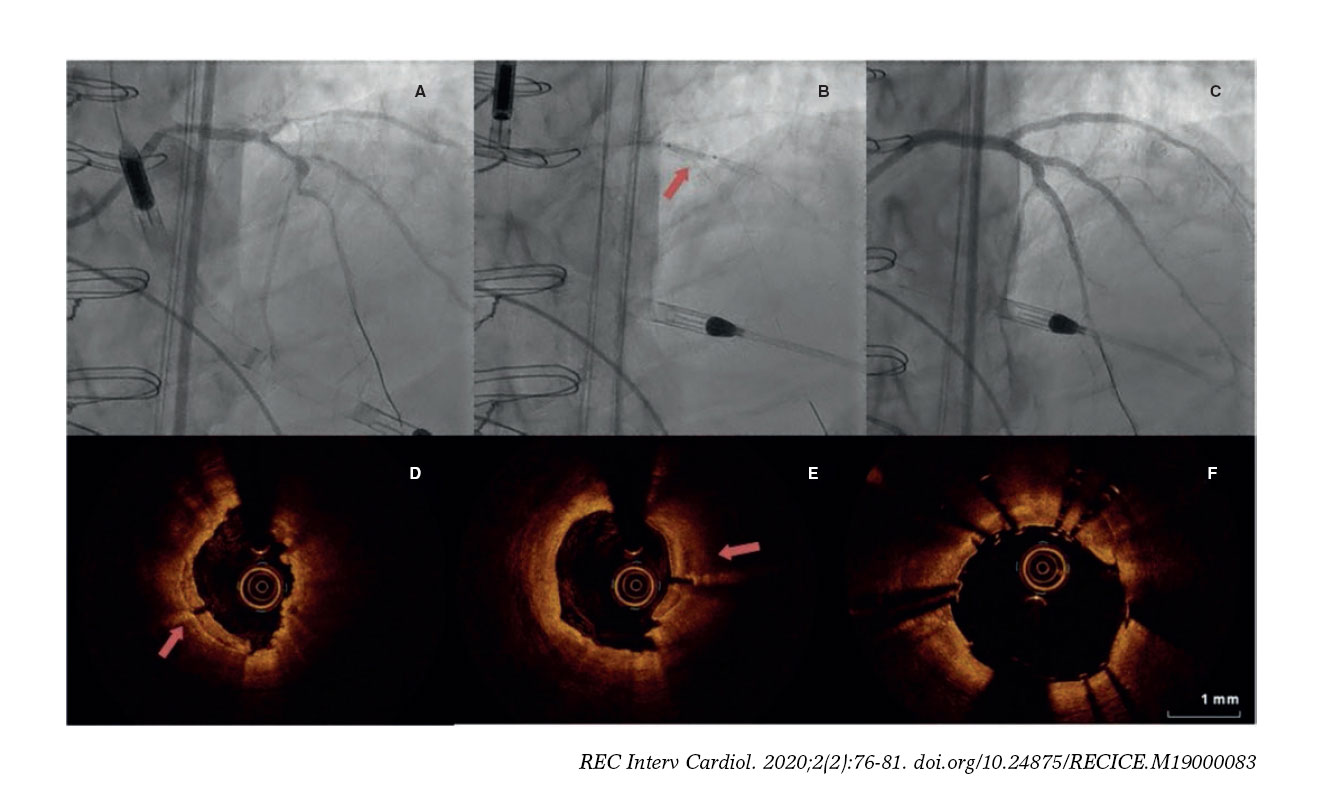

From recintervcardiol.org

Intracoronary lithotripsy in a highrisk realworld population. First Complete Trial Oct Substudy — the multivessel immediate versus staged revascularization in acute myocardial infarction (multistars ami). This oct substudy provides important. among 4,041 patients randomized in the complete trial, nonculprit lesion stenosis severity was measured using qca in the angiographic core. Complete Trial Oct Substudy.